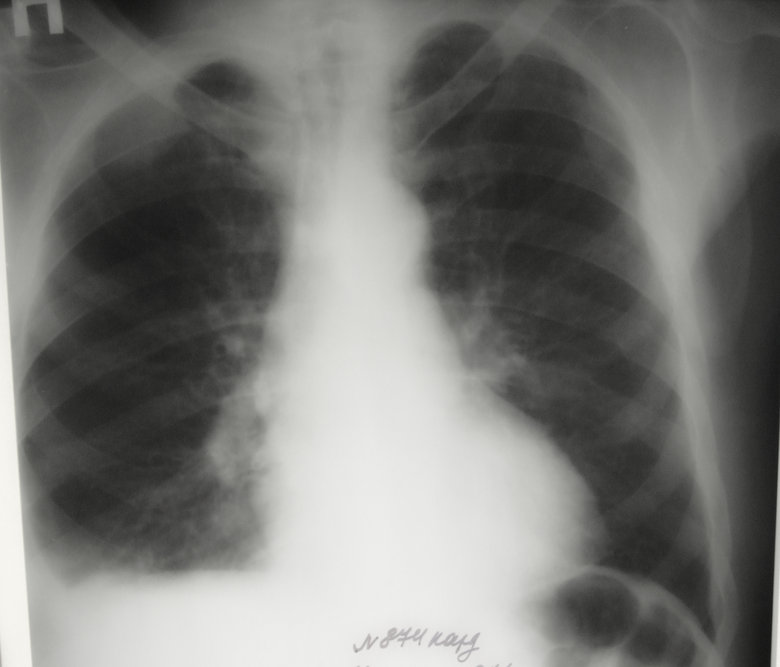

Центральный, справа

Обсуждалось в Госпитале Ослабленных Сердец